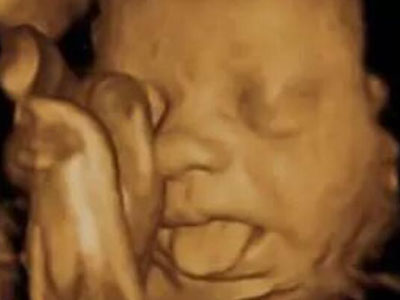

扮鬼脸

胎宝宝在娘胎里就是“戏精”:吸吮手指、啃脚丫、吧唧嘴、抠鼻子、吐舌头、微笑、皱眉......表情贼丰富了!代妈第一次给胎宝宝做四维彩超时有没有惊讶到?我那会儿开心死了!原来,他很早就学会表达自己的感受了,还真是人精!